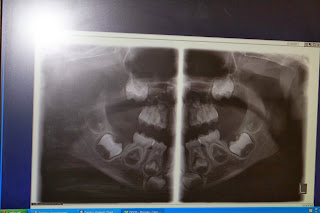

See his big boy teeth growing?

When we left he said that he really liked the dentist and he wasted no time asking me to show Dad the picture of his his big boy teeth growing.